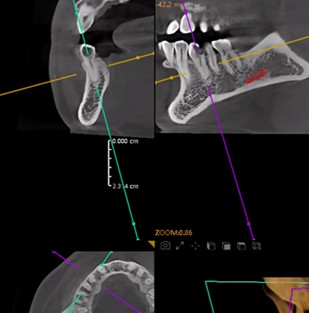

Preoperative Images

May 4, 2025: Extraction of the affected tooth.

Immediate implant placement (first-stage surgery) was performed right after tooth extraction.

Postoperative CT scans and intraoral photographs were obtained.